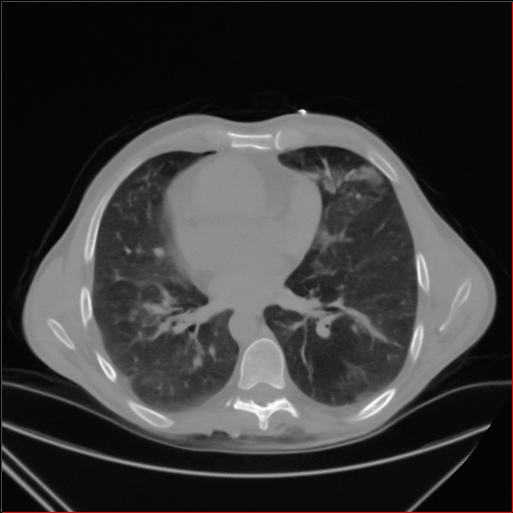

Figure 2: Qualitative comparison across axial (top row), sagittal (middle row), and coronal (bottom row) views. Columns correspond to different methods. MAISI-DDPM and MAISI-v2 in this figure are unconditional synthesis which do not use ControlNet or segmentation maps.

Qualitative Evaluation:

Figure 2 presents representative slices from the axial, sagittal, and coronal planes. GenerateCT (hamamci2024generatect) is a 2D model, so it lacks inter-slice consistency, leading to poor image quality in the sagittal and coronal views. MedSyn (xu2024medsyn) produces noticeably blurry results with mosaic-like artifacts, such as region inside the red box. HA-GAN (sun2022hierarchical) generates visually sharp images but with mosaic-like artifacts, such as region inside the red box. Also, its voxel spacing is not available, which limits its applicability in real-world medical imaging tasks. Moreover, all three methods are restricted to synthesizing small anatomical regions. In contrast, both MAISI and MAISI-v2 are capable of generating high-quality 3D volumes that span larger body regions while preserving fine anatomical details and realistic structure.